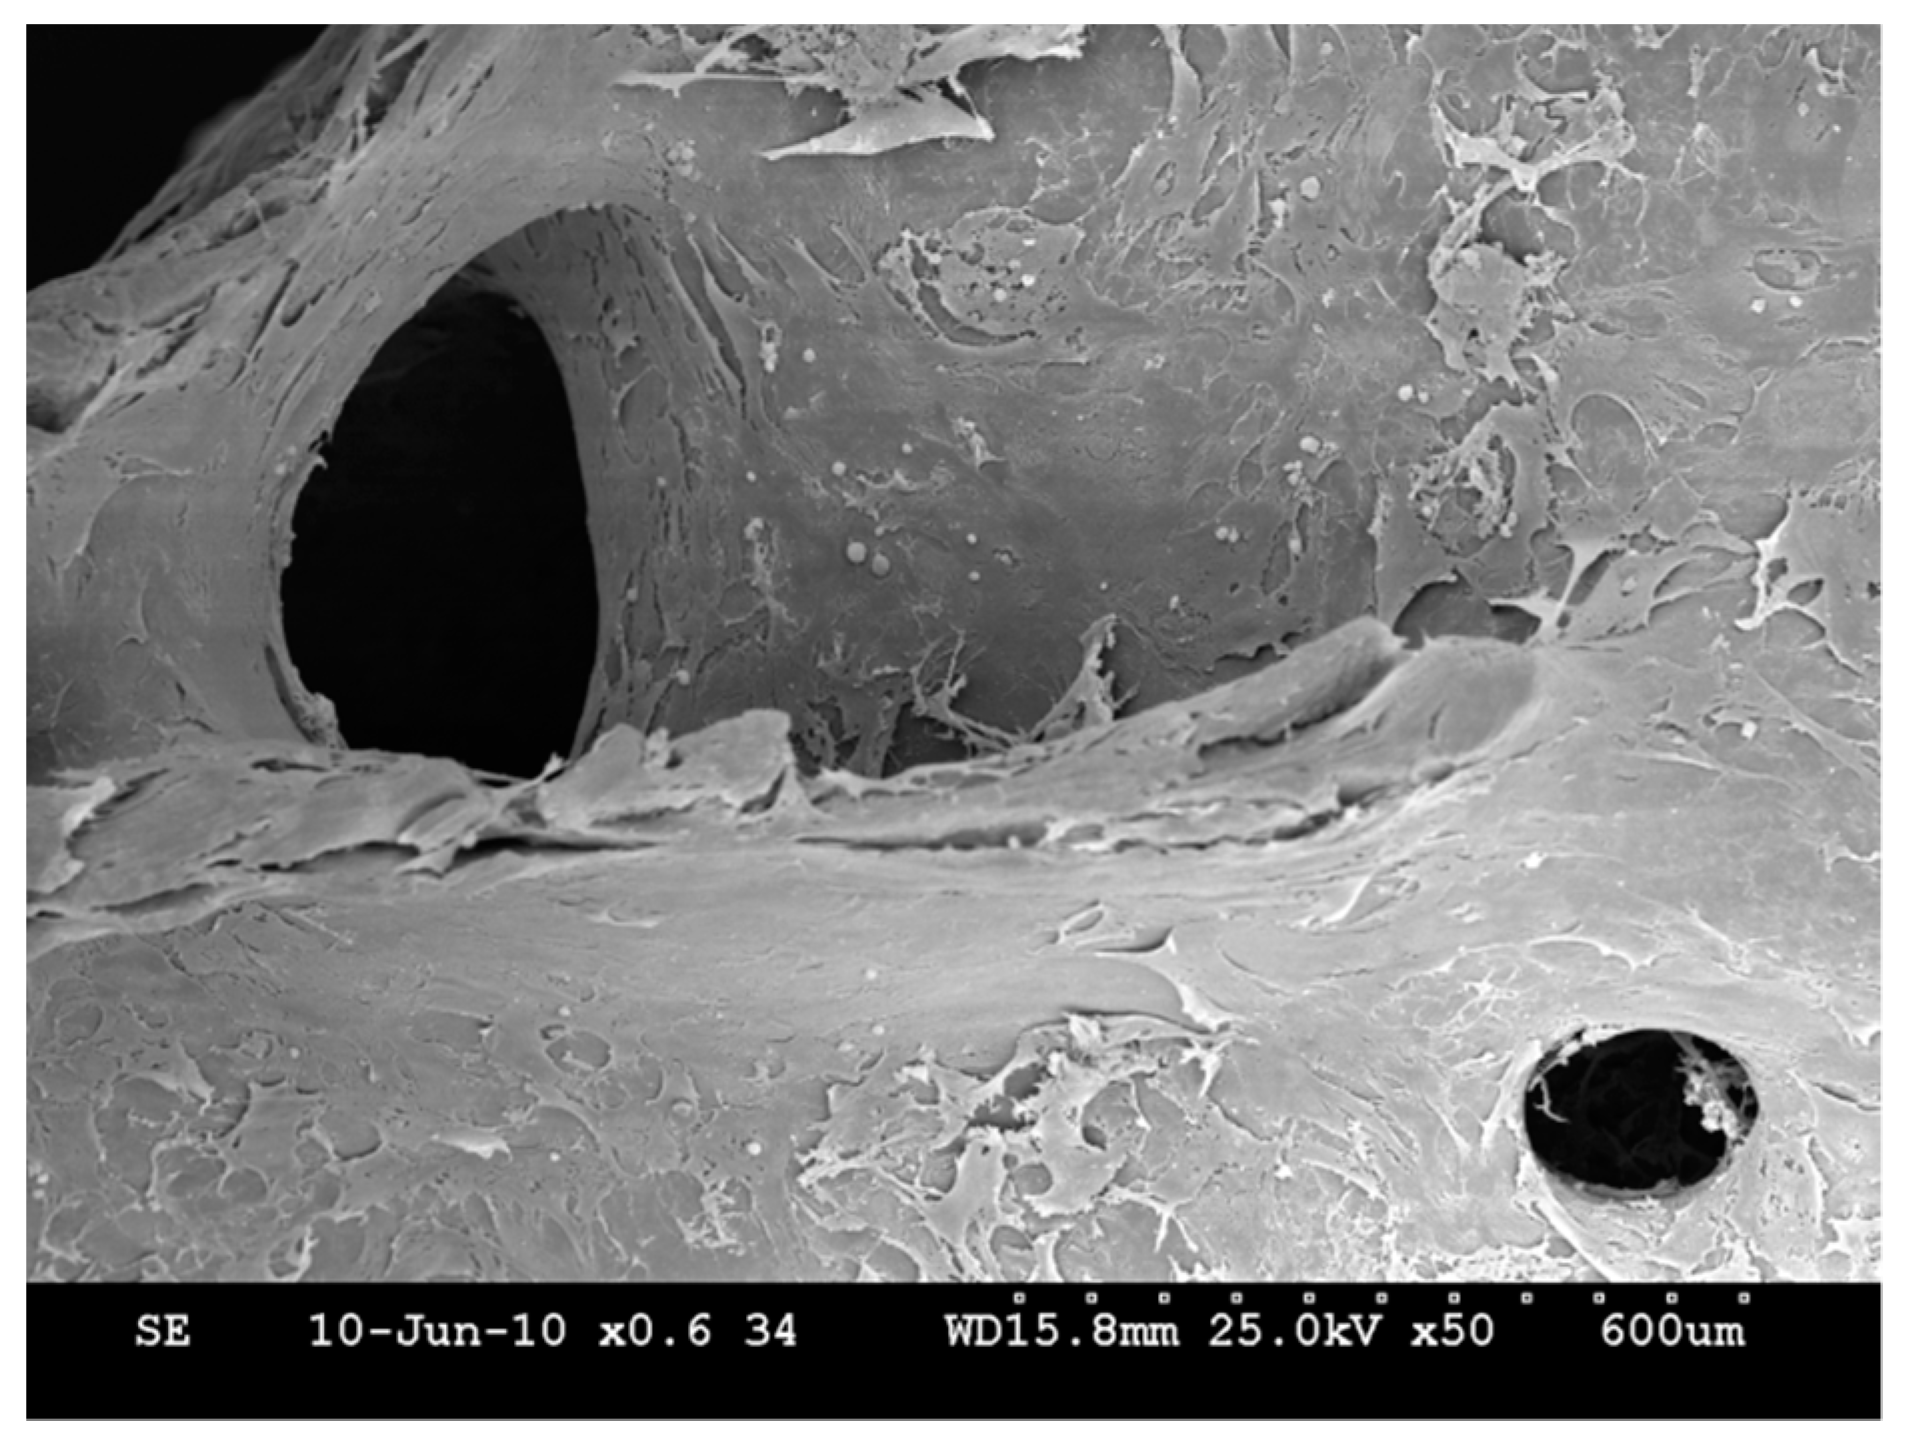

The ovine USSCs seeded onto the HA-scaffolds were present on the outer surface of the biomaterial after seven days in vivo (Figure 2). At further follow-up, cell viability testing revealed that the cells completely covered the outer surface of the scaffold but were also detected at deeper levels up to 1 mm from the surface.

Figure 2.

SEM picture of HA scaffold with USSC at day 10.